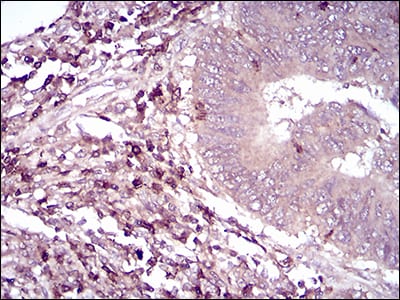

分类: 科研抗体货号: 30726别名: TRIM63; IRF; SMRZ; MURF2; RNF28应用: IHC,IF,FCM反应种属: Human